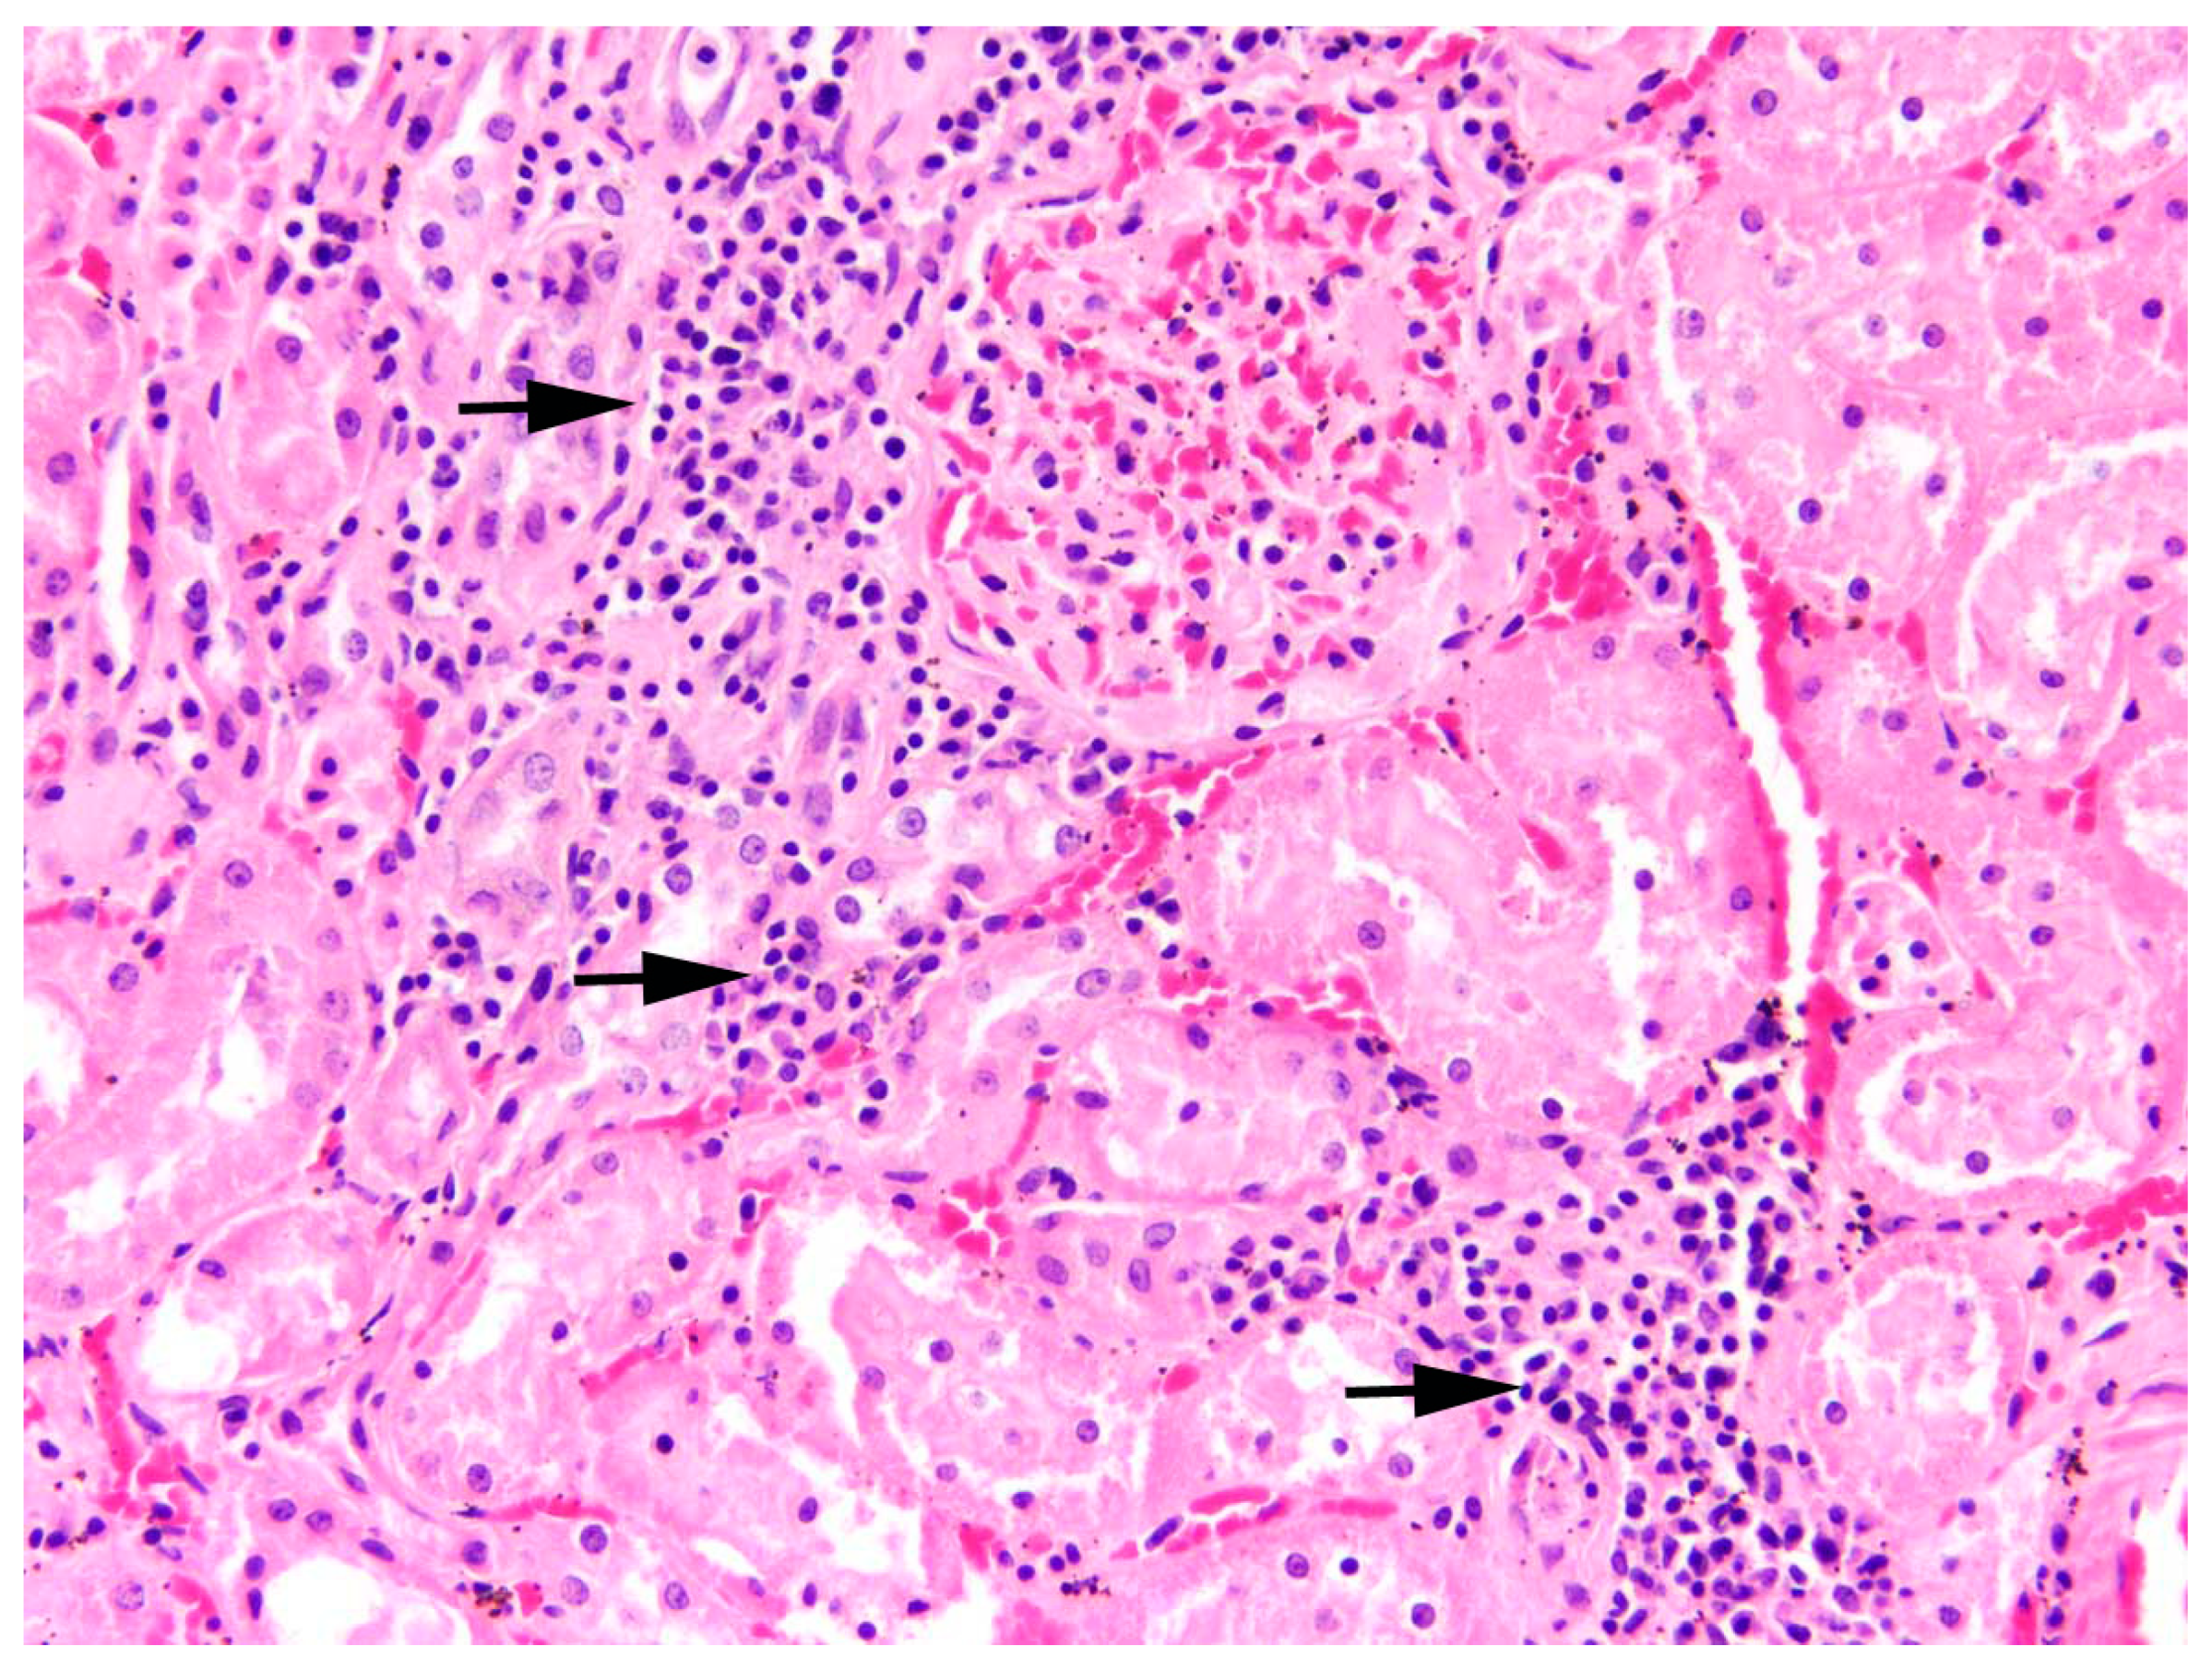

Kidneys: In one-third of the studied animals, inflammation of the kidneys was found (31.0%, n = 48). Whereas no significant effect of hunting ground or sex was observed, age (p = 0.01, Table S1) and sampling year (p = 0.007, Table S1) revealed a significant effect on the presence of nephritis. The prevalence of nephritis was the highest in 2016 (47.2%, n = 25; Figure 11a), with significantly more hares confirmed in post-hoc analyses compared to hares sampled in 2017 (18.8%, n = 9, p = 0.009; Table S2). Between the other sampling years, no significant difference was determined in statistical analyses. Furthermore, significantly more adults were diagnosed with nephritis (37.6%, n = 38) than juveniles (18.5%, n = 10, p = 0.01; Figure 11b).

All inflammations of the kidneys were non-purulent, with interstitial infiltrations of lymphocytes, macrophages, and plasma cells (Figure 12). In one adult male, fibrosis and depression on the kidney surface were observed.